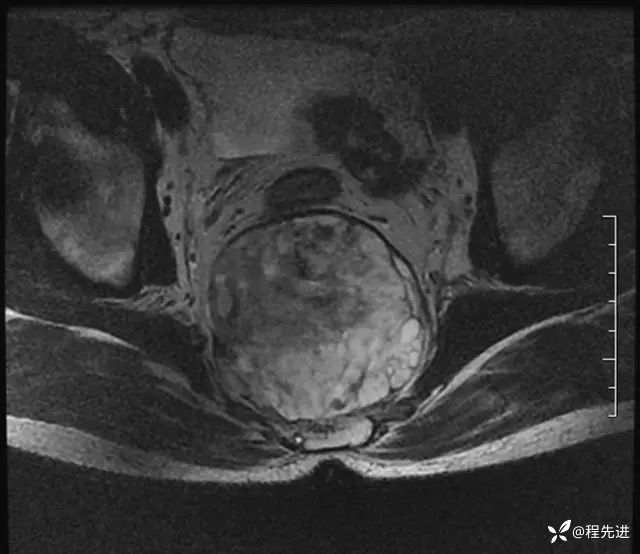

MRI平扫+增强:

T2: